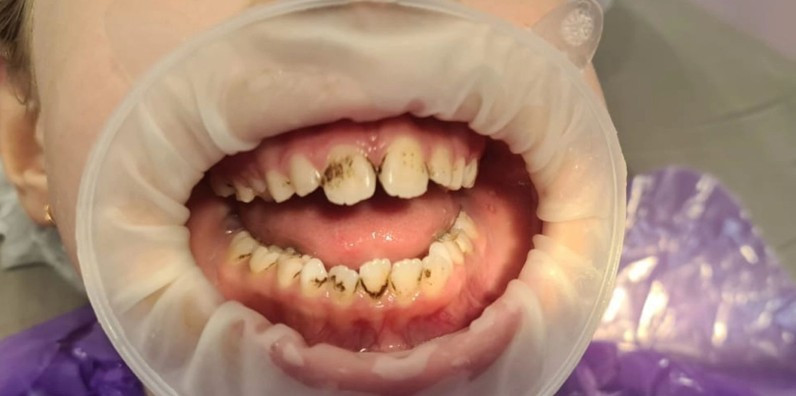

Стоматологическая клиника ГРАНАТ

Чистка зубов Air-flow